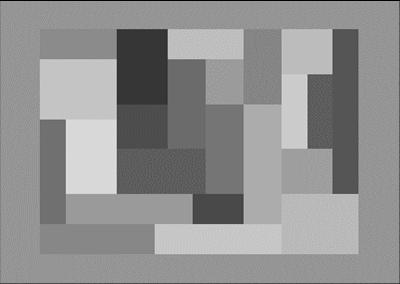

Visualization:

Anatomical or functional volumes and statistical (parametric or not) maps can be displayed in two separate windows with linked cursors to localize a specific position (see Figure 2). Our visualization tool can be used in two ways. First, you can use it to visualize the results of a temporal or spatial ICA (as displayed in Figure 2 for sICA). The time slider here indicates the rank of the component currently visualized (among all those extracted) and the displayed time course represents the values of the spatial component for the selected voxel (blue circle). Second, you can use it to visualize raw fMRI data. In this case the time slider would represent the time course of the selected voxel, i.e. the MR signal values across time measured at the voxel position.